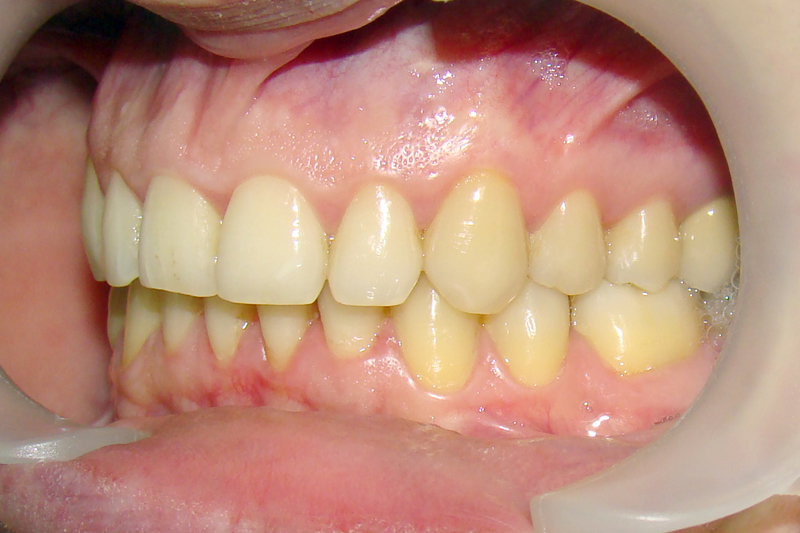

А это уже молодой человек 10 лет. Тоже получилось справиться без удаления. Хоть оно и было показано. Но мальчик очень упорно носил специальные аппаратики и резиночки. Покажу со всех сторон. Этот случай победил в конкурсе на конференции